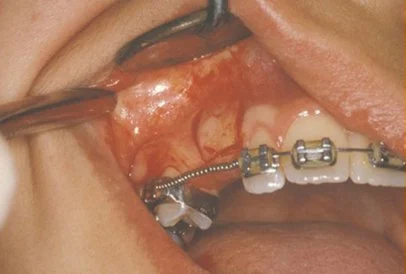

In cases where the eyeteeth will not erupt spontaneously, the orthodontist and oral surgeon will work together to get these teeth to erupt. Each case must be evaluated on an individual basis, but treatment will usually involve a combined effort between the orthodontist and the oral surgeon. The oral surgeon will expose and bracket the impacted eyetooth.

Exposure and Bracketing of an Impacted Cuspid

The surgery to expose and bracket an impacted tooth is a very straightforward surgical procedure that is performed in the oral surgeon’s office. For most patients, it is performed using laughing gas and local anesthesia. In selected cases it will be performed under IV sedation if the patient desires to be asleep, but this is generally not necessary for this procedure. If the procedure only requires exposing the tooth with no bracketing, the time required will be shortened by about one half. These issues will be discussed in detail at your preoperative consultation with your doctor.